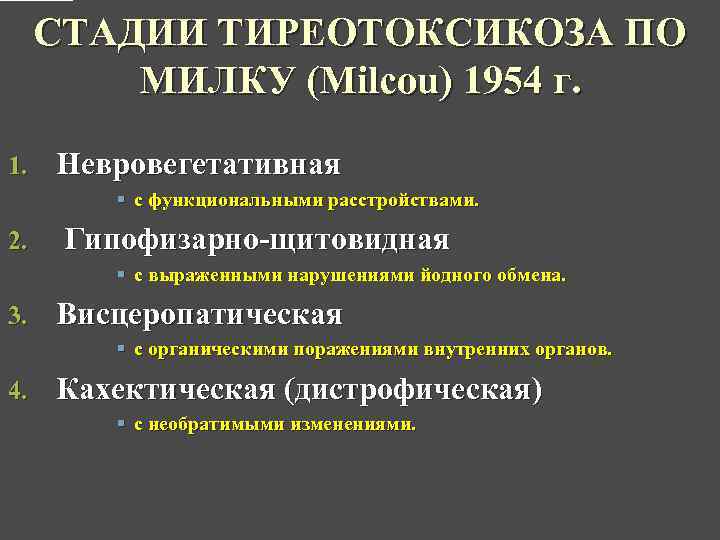

СТАДИИ ТИРЕОТОКСИКОЗА ПО МИЛКУ (Milcou) 1954 г. 1. Невровегетативная § с функциональными расстройствами. 2. Гипофизарно-щитовидная § с выраженными нарушениями йодного обмена. 3. Висцеропатическая § с органическими поражениями внутренних органов. 4. Кахектическая (дистрофическая) § с необратимыми изменениями.